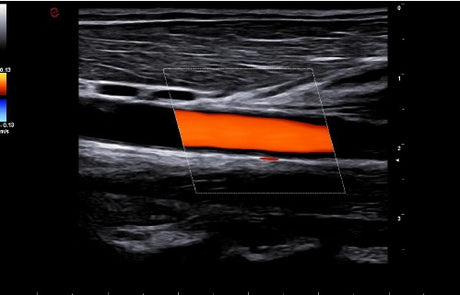

La qualité d’image est au cœur de la philosophie Esaote. Grâce à ses sondes de dernière génération et à son traitement du signal avancé, la marque permet une visualisation fine des structures anatomiques, même les plus profondes. Leurs échographes intègrent des écrans tactiles haute résolution, une interface claire et une connectivité complète, favorisant un flux de travail rapide et efficace.

Les échographes Esaote offrent une restitution d’image d’une grande précision, permettant un diagnostic fiable dans toutes les spécialités. Le traitement numérique optimise le contraste et la netteté, réduisant les artefacts et améliorant la détection des tissus pathologiques. Ces performances sont particulièrement appréciées en gynécologie, où la lisibilité des structures pelviennes ou obstétricales est déterminante.